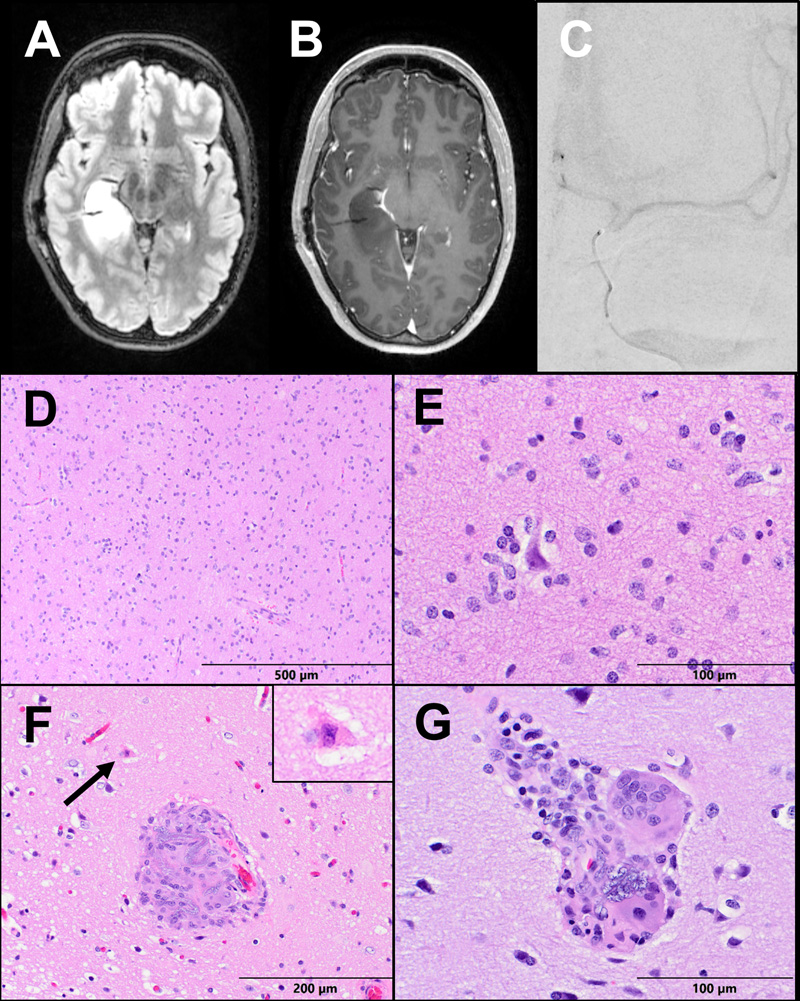

Figure 1: Case 1 Imaging and Pathology. (A) Axial T2-FLAIR and (B) T1 post-contrast sequences of a brain MRI demonstrating a non-enhancing infiltrative and expansile T2-hyperintense mass centered within the right superior temporal gyrus. (C) A PA view of digital subtraction angiogram demonstrating a microcatheter within the right internal carotid artery. (D-E) The tumor resection demonstrates a moderately to highly cellular infiltrating glioma, with significant nuclear atypia and scattered mitoses (arrow). (F-G) Parenchymal vessels within the resection display giant cell vasculitis and contain basophilic granular foreign material consistent with hydrophilic polymer.

A 55-year-old right-handed man presented with new-onset generalized tonic-clonic seizures. Magnetic resonance imaging (MRI) revealed a non-enhancing infiltrative and expansile T2-hyperintense mass centered within the right superior temporal gyrus (Fig. 1a-b). The patient underwent bilateral Wada testing. Vascular access was obtained via the right femoral artery using the modified Seldinger technique. A 5-French angled glide diagnostic catheter was introduced over a 0.035 Terumo Glidewire into the descending thoracic aorta and then the cervical internal carotid artery under direct fluoroscopic visualization. A Codman Prowler Select Plus infusion microcatheter with a Synchro 2 microwire was used to catheterize the internal carotid artery just distal to the posterior communicating artery. An angiographic run was performed to confirm catheter position prior to Brevital (methohexitol) infusion (Fig. 1c). The Wada test demonstrated clear left hemisphere language dominance and greater left hemisphere memory support.

Evaluation of the primary resection specimen revealed a moderately to highly cellular diffusely infiltrating glioma. There was significant pleomorphism and focally frequent mitoses, but no microvascular proliferation or necrosis, meeting histologic criteria for anaplastic astrocytoma, WHO Grade III (Fig. 1d-e). Molecular analysis by next-generation sequencing (NGS) and microarray revealed features of primary IDH-wildtype glioblastoma, including EGFR amplification, and the tumor was upgraded to WHO Grade IV.5 Additionally noted on pathologic examination were scattered foci of giant cell vasculitis and intravascular foreign material. The foreign material was granular, blue-gray and non-polarizable, morphologically consistent with hydrophilic polymer material. No surrounding ischemic changes were identified (Fig. 1f-g).